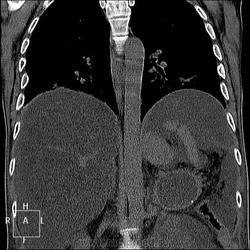

. Не станете же Вы утверждать, что бери-бери или гиповитаминоз В1 присущи исключительно мужчинам? Согласна исключить из вероятностей патогенеза этого пациента Синдром Мейгса:).  . Здесь печень замещена жировой тканью, гепатоциты отсутствуют на 90-95%. Разовьём тему функции печени?

. Здесь печень замещена жировой тканью, гепатоциты отсутствуют на 90-95%. Разовьём тему функции печени?

Тут воды полно, саму печень надо поискать, я постаралась поиграть окнами, чтоб её было видно. Не особо и увеличена. Уже.

Печень по цвету (плотности) должна быть почти такой же, как и селезенка (50-70 единиц), а в данном случае 10 единиц, вода в брюшной полости 5-7 единиц. Так что нормальных гепатоцитов там кот наплакал.

Интерстициальный отек легких. Хронический калькулезный панкреатит. Киста хвоста поджелудочной железы, без биопсии уверенно раковое перерождение не исключить. Киста сальниковой сумки /вероятно тоже панкреатического генеза/. Жировой гепатоз печени с портальным циррозом /биопсия/. Камень устья? пузырного протока. Геморрагические кисты почек??? Асцит.

Камень в месте слияния пузырного и общего печеночного протоков. Думаю, что корковые и медуллярные кисты почек, да, но может ли быть в них кровоизлияние, вызванное ДВС-синдромом, например, или они изначально были геморрагическими - не знаю. Четкие контуры у кисточек, формой на микроинфаркты не тянут.